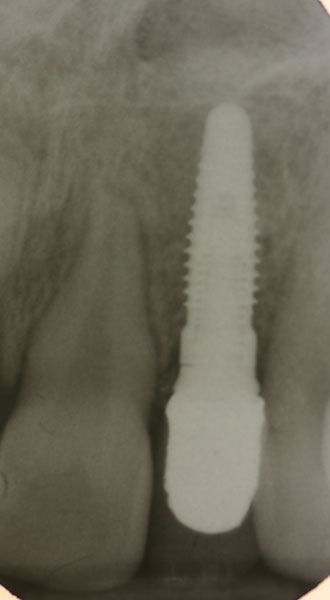

Fall: Einzelzahnlücke nach Zahnextraktion

![]() |